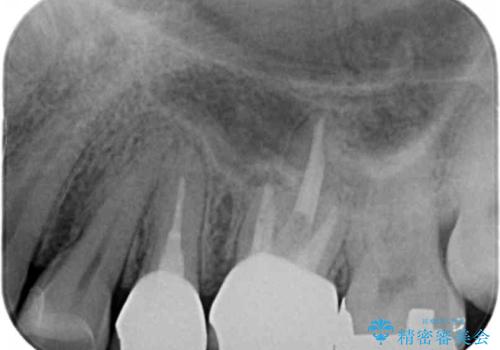

セラミックインレーと根管治療を伴うセラミッククラウン

- 根管治療の難易度が高く他院で放置か抜歯を提案され、治療をご希望され当院へと来院されました。

X線写真より大きな根尖病変が認められ根管治療および補綴処置、手前の歯は虫歯の再発による銀歯のやりかえが必要な状態です。

根管が非常に細くアプローチが難しいような場合、マイクロスコープを用いた精密根管治療を行うことで治療を成功へと導くことができる場合があります。